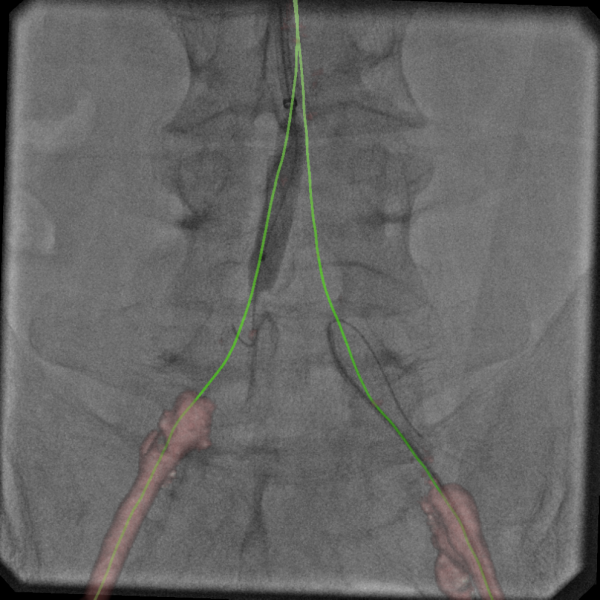

As the complexity of interventional procedures continues to grow, angiography system vendors are developing software to better help visualize the anatomy and guide procedures. At RSNA 2015, GE Healthcare showcased the latest of these guidance aids with its Assist collection of interventional imaging software packages. These are designed for specific clinical subspecialists and complex endovascular procedures to help clinicians perform procedures with greater accuracy and dose efficiency. The suite offers simple-to-use fusion imaging for CT 3-D image reconstructions that can be overlaid or fused with live angiography in the cath lab.

The software packages include Vessel Assist to navigate vessels for chronic total occlusions (CTO), transjugular intrahepatic portosystemic shunt (TIPS) and interventional neuroradiology arteriovenous malformation (AVM) and aneurysms. EVAR Assist is designed for vascular surgery and endovascular aortic repair (EVAR). Needle Assist is for bone interventions and pelvic bone osteosynthesis. FlightPlan for Liver is for interventional oncology liver embolization. Valve Assist aids transcatheter aortic valve replacement (TAVR). PCI Assist helps navigate interventional cardiology complex percutaneous coronary interventions (PCI).

The Assist packages offer allow easy anatomy segmentation and extraction of the 3-D anatomy in two clicks, measuring the vascular with accuracy like length and diameter, and adding landmarks.